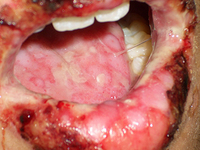

Oral and mucosal ulcerations, carbamazepine induced Stevens-Johnson syndrome

Khoo AB, Ali FR, Yiu ZZ, et al. Carbamazepine induced Stevens-Johnson syndrome. BMJ Case Rep. 2016;2016. pii: bcr2016214926. Used with permission